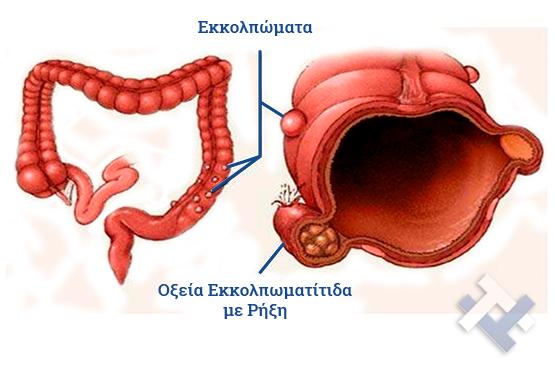

- Εκκολπωμάτωση (Εκκολπωματίτιδα) σιγμοειδούς

- Εκκολπωμάτωση (Εκκολπωματίτιδα) σιγμοειδούς

Ο Γενικός Χειρουργός Λιάγκος Γεώργιος MD PhD εκτελεί τις επεμβάσεις Λαπαροσκοπικά, Ενδοσκοπικά, Ανοιχτά Ελάχιστα Επεμβατικά και με Laser. Η θεραπεία εξατομικεύεται σε κάθε ασθενή ανάλογα με τις ανάγκες του. Αναλαμβάνει περιπτώσεις όπως κήλες και κοιλιοκήλες (αντιμετώπιση βουβωνοκήλης, αντιμετώπιση ομφαλοκήλης, θεραπεία επιγαστρικής κήλης, κήλη των αθλητών (Σύνδρομο κοιλιακών προσαγωγών), αντιμετώπιση μετεγχειρητικής κήλης, θεραπεία Μηροκήλης), πέτρες στη χοληδόχο κύστη, λαπαροσκοπική χολοκυστεκτομή, αντιμετώπιση Κύστη Κόκκυγος με λέιζερ (laser), παθήσεις πρωκτού, χειρουργική laser σύγχρονων κυκλικών ινών (αιμορροΐδες αντιμετώπιση, θεραπεία αιμορροϊδων με laser (LHP), αφαίρεση αιμορροΐδων με υπερήχους (HALL-RAR), χωρίς Χειρουργείο με ελαστικούς δακτυλίους (Τεχνική BARON-RBL), θεραπεία ραγάδας πρωκτού (Ραγάδα δακτυλίου), θεραπεία περιεδρικού συριγγίου, θεραπεία περιεδρικού αποστήματος, κονδυλώματα πρωκτού Θεραπεία, δερματικό ράκος (Skin tag) εκτομή, αντιμετώπιση Kνησμού, καρκίνος πρωκτού θεραπεία), παθήσεις Δέρματος, χειρουργική με laser CO2, αφαίρεση μορφωμάτων δέρματος - βιοψίες, αφαίρεση ελιάς (Σπίλου), σμηγματογόνος κύστης θεραπεία, αφαίρεση λιπώματος, είσφρυση όνυχος χειρουργείο, καρκίνος δέρματος θεραπεία, οξεία σκωληκοειδίτιδα, παθήσεις Λεπτού και Παχέος Εντέρου, ειλεός λεπτού εντέρου, εκκολπωμάτωση (Εκκολπωματίτιδα) σιγμοειδούς, καρκίνος παχέος εντέου, κολοστομίες, port χημειοθεραπείας κ.α.

Ο Γενικός Χειρουργός Λιάγκος Γεώργιος MD PhD εκτελεί τις επεμβάσεις Λαπαροσκοπικά, Ενδοσκοπικά, Ανοιχτά Ελάχιστα Επεμβατικά και με Laser. Η θεραπεία εξατομικεύεται σε κάθε ασθενή ανάλογα με τις ανάγκες του. Αναλαμβάνει περιπτώσεις όπως κήλες και κοιλιοκήλες (αντιμετώπιση βουβωνοκήλης, αντιμετώπιση ομφαλοκήλης, θεραπεία επιγαστρικής κήλης, κήλη των αθλητών (Σύνδρομο κοιλιακών προσαγωγών), αντιμετώπιση μετεγχειρητικής κήλης, θεραπεία Μηροκήλης), πέτρες στη χοληδόχο κύστη, λαπαροσκοπική χολοκυστεκτομή, αντιμετώπιση Κύστη Κόκκυγος με λέιζερ (laser), παθήσεις πρωκτού, χειρουργική laser σύγχρονων κυκλικών ινών (αιμορροΐδες αντιμετώπιση, θεραπεία αιμορροϊδων με laser (LHP), αφαίρεση αιμορροΐδων με υπερήχους (HALL-RAR), χωρίς Χειρουργείο με ελαστικούς δακτυλίους (Τεχνική BARON-RBL), θεραπεία ραγάδας πρωκτού (Ραγάδα δακτυλίου), θεραπεία περιεδρικού συριγγίου, θεραπεία περιεδρικού αποστήματος, κονδυλώματα πρωκτού Θεραπεία, δερματικό ράκος (Skin tag) εκτομή, αντιμετώπιση Kνησμού, καρκίνος πρωκτού θεραπεία), παθήσεις Δέρματος, χειρουργική με laser CO2, αφαίρεση μορφωμάτων δέρματος - βιοψίες, αφαίρεση ελιάς (Σπίλου), σμηγματογόνος κύστης θεραπεία, αφαίρεση λιπώματος, είσφρυση όνυχος χειρουργείο, καρκίνος δέρματος θεραπεία, οξεία σκωληκοειδίτιδα, παθήσεις Λεπτού και Παχέος Εντέρου, ειλεός λεπτού εντέρου, εκκολπωμάτωση (Εκκολπωματίτιδα) σιγμοειδούς, καρκίνος παχέος εντέου, κολοστομίες, port χημειοθεραπείας κ.α.